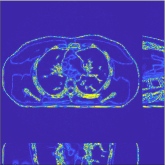

This section compares the reconstruction quality and runtime among the proposed MBIR method, PWLS-ST-, and other three MBIR methods, PWLS-EP, PWLS-DL, and PWLS-ST-. Table I shows that, for both 2D and 3D sparse-view CT reconstructions of the XCAT phantom, the proposed PWLS-ST- model outperforms PWLS-EP and PWLS-ST- in terms of RMSE. In addition, PWLS-ST- using a square transform (of size ) achieves lower RMSE than PWLS-DL using an overcomplete dictionary (of size ) for 2D sparse-view reconstructions. Fig. 3(a) and Fig. 4 show the reconstructed images for 2D and 3D phantom experiments, with different reconstruction models and different number of views. (See the corresponding error maps in the supplement.) The proposed PWLS-ST- consistently gives more accurate image reconstructions compared to other MBIR methods. Specifically, PWLS-ST- has smaller errors in the heart region (see zoom-ins in Fig. 3(a)) of 2D reconstructions than PWLS-DL and PWLS-ST-. In addition, compared to PWLS-ST-, PWLS-DL and PWLS-ST- have some ringing artifacts around the edges with high transition, e.g., edges between air and soft tissues. (See a comparison of profiles of PWLS-ST- and PWLS-ST- in the supplement.) In particular, PWLS-ST- and PWLS-DL give more visible ringing artifacts for 2D reconstruction from fewer views, and PWLS-ST- has these ringing artifacts for 3D reconstructions regardless of the number of views (see zoom-ins in Fig. 4). Table II reports runtimes of different MBIR methods in reconstructing the -views XCAT phantom scan. (FBPConvNet is a non-MBIR method and its runtime for processing a image is approximately one second with a TITAN Xp GPU.) While providing better reconstruction quality, the proposed Algorithm 1 of PWLS-ST- has shorter runtime compared to the algorithms of PWLS-DL and PWLS-ST- in Section III-A. Similar to the PWLS-EP algorithm, the reconstruction time of the PWLS-DL, PWLS-ST-, and PWLS-ST- algorithms can be further reduced by using ordered subsets [51].

Fig. 3(b) shows that when tested on the clinical scan data, the proposed PWLS-ST- method improves reconstruction quality in terms of noise and artifacts removal (e.g., see zoom-ins for soft-issue regions), and edge preservation (e.g., see zoom-ins for bone regions), compared to PWLS-EP and PWLS-ST-. Compared to PWLS-DL, PWLS-ST- achieves comparable image quality, but requires less computational complexity.

The benefit of the proposed PWLS-ST- over PWLS-ST- can be explained when there exist some outliers for some : in (12) gives equal emphasis to all sparse codes – from small to large coefficients that generally correspond to edges in low- and high-contrast regions, respectively – in estimating ; however, PWLS-ST- adjusts to mainly minimize the outliers, i.e., it may not pay enough attention to reconstruct regions with small coefficients. The histogram results in Fig. 1 reveal model mismatch of PWLS-ST- over the iterations. Fig. 3, Fig. 4, and Table I show that PWLS-ST- can moderate model mismatch, and provides more accurate reconstruction than PWLS-ST-.

![]() |

| (a) 2D fan-beam CT experiments |

| (b) 3D axial cone-beam CT experiments |